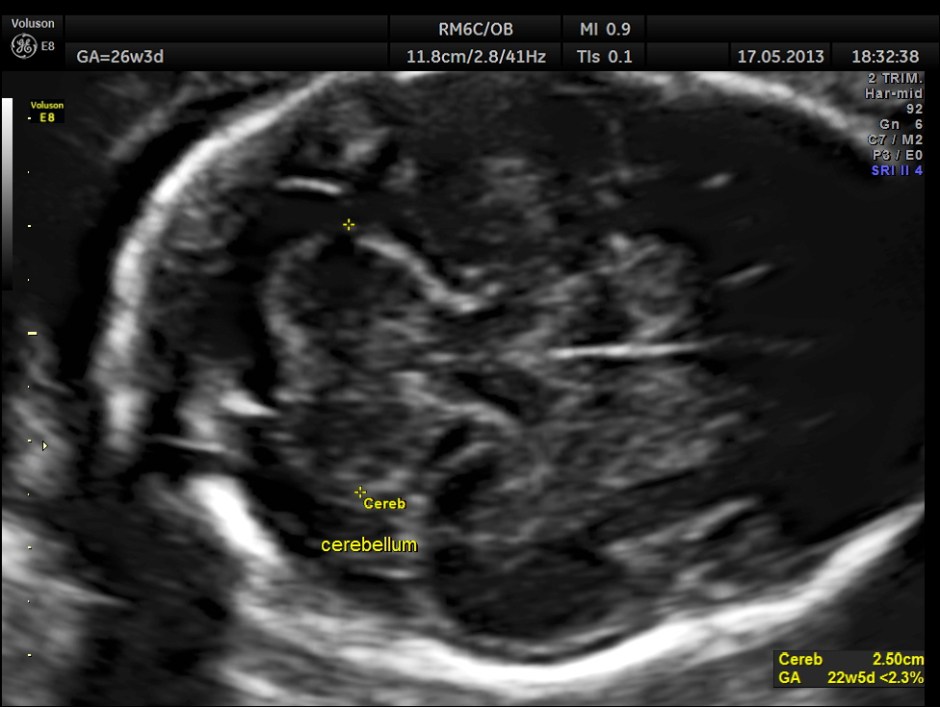

The images are given below.

Cerebellum appears relatively smaller and corresponds to a GA of 22 to 23 weeks. Usually the cerebellum corresponds very closely to the GA and would be very useful to follow in cases of IUGR.

Cerebellum was < 2.3 %tile , suggestive of possible cerebellar hypoplasia. Unfortunately this patient was lost for follow up .